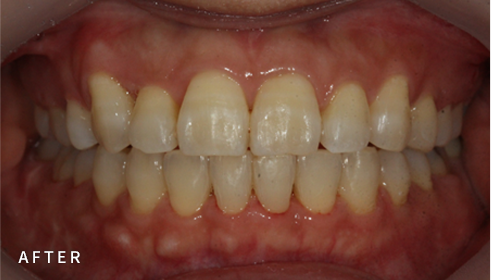

• 구강 및 얼굴 사진 촬영

치아의 형태, 교합 양상 뿐만 아니라

돌출 및 비대칭 정도 등을 촬영하여 진단에 활용합니다.